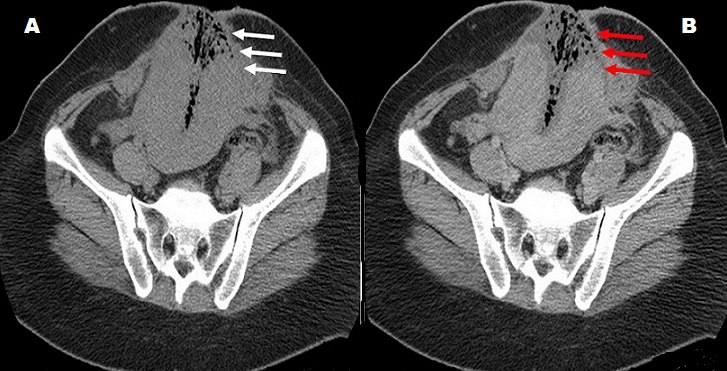

Il s’agit d’une patiente de 42 ans, deuxième geste, deuxième parité, admise pour prise en charge d’un myome utérin interstitiel. Les suites opératoires ont été marquées par une infection cutanée associée à une éventration utérine. A l’examen, la patiente était fébrile à 39.5°C, associée à une éviscération de l’utérus avec issu de pus verdâtre à travers le site opératoire. Le bilan biologique réalisé montrait un taux d’hémoglobine à 12g/dl, une hyperleucocytose à polynucléaire neutrophile 15000/uL et la C Réactive Protéine à 320 mg/l. Ces résultats ont conduit à la réalisation d’un complément TDM qui a montré une fistule utero-pariétale avec une éviscération utérine, sans complication digestive associée. L’utérus était également disroté avec un contenu hydro-aérique, faiblement rehaussé en périphérie après contraste, confirmant une surinfection associée. La prise en charge chirurgicale a été effectuée avec curetage de la cavité utérine à travers la brèche de perforation qui a été par la suite suturée. Ce cas met en exergue une complication rare de perforation utérine dans les suites opératoires d’une myomectomie utérine.